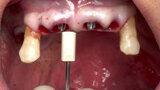

The fully digital Pro Arch protocol